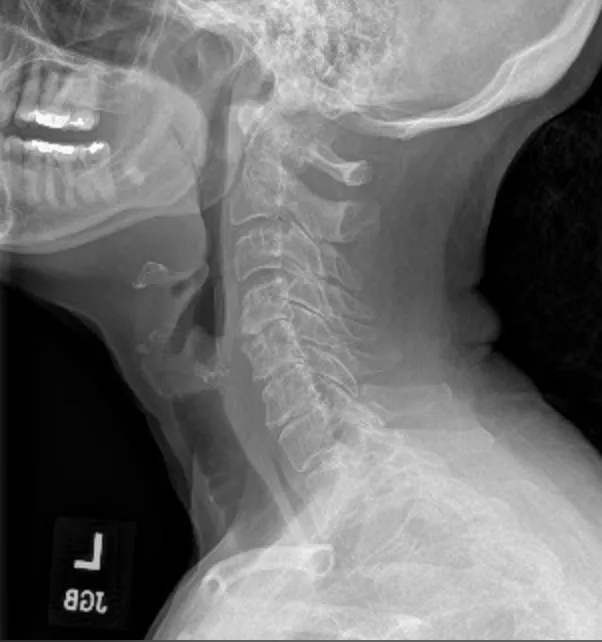

Degenerative disc disease, loss of disc height, disc bulges/herniations, and nerve compression are common findings in patients who may benefit from decompression-based care.

Spinal decompression is a controlled, motorized form of traction designed to reduce pressure inside damaged spinal discs. By creating cycles of gentle distraction and relaxation, decompression can help improve disc hydration and reduce mechanical stress on irritated nerves.